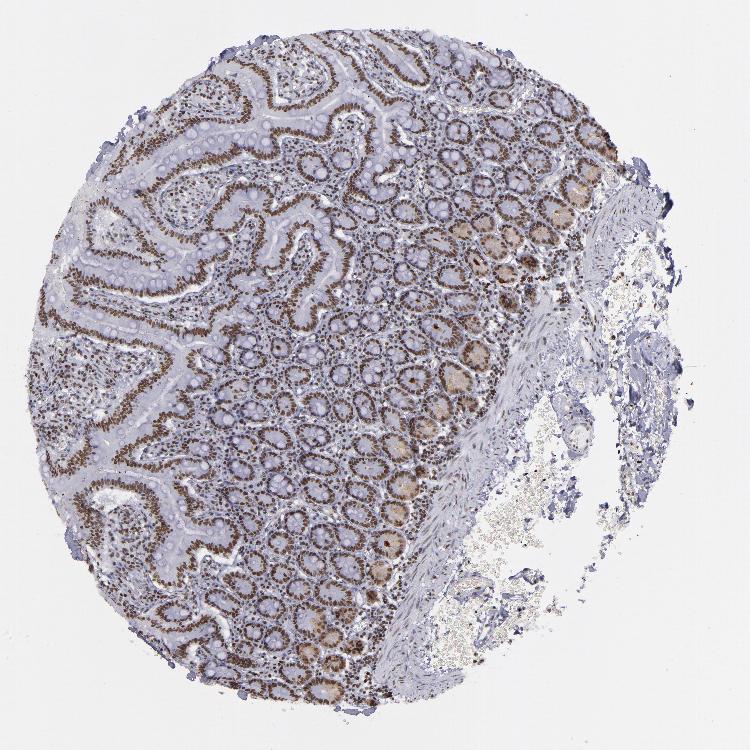

TISSUE PRIMARY DATA SMALL INTESTINE Show tissue menu

Small intestine

SMALL INTESTINE - Antibody stainingi

Antibody staining in the annotated cell types in the current human tissue is reported as not detected, low, medium, or high, based on conventional immunohistochemistry profiling in selected tissues. This score is based on the combination of the staining intensity and fraction of stained cells.

Each image is clickable and will lead to virtual microscopy that enables deeper exploration of all samples and also displays staining intensity scores, fraction scores and subcellular localization as well as patient and tissue information for each sample.

Antibody HPA001907Antibody HPA002735Antibody CAB010451Antibody CAB080271

Glandular cells HighMediumMediumHigh